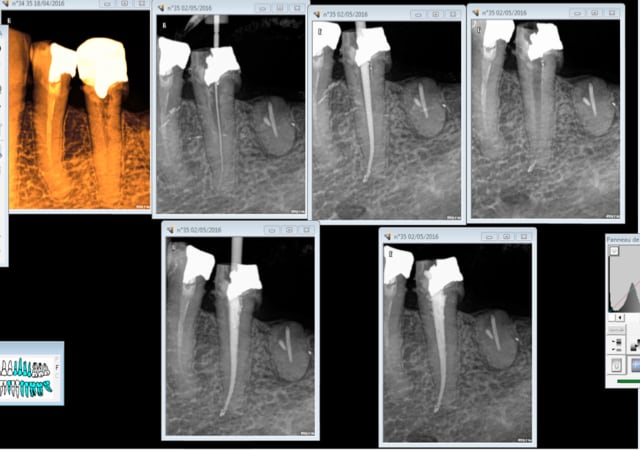

Je reviens sur ce cas à l'image curieuse. patient venu en urgence et je m'étais démerdé pour faire le TT en un RDV quitte à modifier quelque peu mon planning de la journée ( léger retard).

Et là, un gros canal latéral ou un coup de pro-taper retraitement mal placé ??